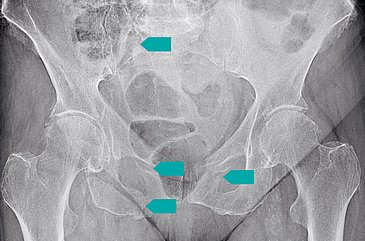

„Beim Beckenbruch gibt es zwei Altersgipfel“, erklärt der leitende Oberarzt und Leiter des Bereichs Beckenchirurgie am Uni-Klinikum Erlangen, Prof. Dr. Hans-Georg Palm. „Einen bei Männern zwischen 20 und 30 Jahren, die ein Hochrasanztrauma erleiden. Das heißt: Es wirkt eine hohe kinetische Energie auf den Körper ein – z. B. bei einem Verkehrsunfall oder einem Sturz aus großer Höhe. Der zweite Gipfel liegt bei älteren Frauen mit osteoporotisch veränderten Knochen, die leichter brechen – auch schon bei einem einfachen Sturz.“ Die Bruchmorphologie ist bei beiden Gruppen sehr unterschiedlich: Während bei großen Unfallverletzungen der Schaden sofort erklär- und sichtbar wird, sind Beckenbrüche bei alten Menschen oft nicht so schnell diagnostizierbar. „Manchmal klagt jemand schon längere Zeit über stark ausgeprägte Schmerzen in der Hüfte, im Rücken oder in der Leiste, aber erst bei einer Computertomografie (CT) oder einer Magnetresonanztomografie wird eine Fraktur erkennbar“, weiß Prof. Palm. In diesem Zusammenhang forscht der Beckenexperte schon seit mehreren Jahren zur Dual-Energy-CT, die Gewebe sehr differenziert darstellt und somit Altersbeckenbrüche noch besser sichtbar macht. Das Uni-Klinikum Erlangen nimmt zudem an der bundesweiten „AG Becken III“ der Deutschen Gesellschaft für Unfallchirurgie e. V. teil, die unter anderem Daten zur Epidemiologie und zu neuen operativen Techniken sammelt.

Angesichts der demografischen Entwicklung werden Altersbeckenbrüche zunehmen – also die Zahl jener Patienten, die aufgrund spröder Knochen schon bei „normalen“ Stürzen sogenannte Fragilitätsfrakturen erleiden. „Beim Becken eines alten Menschen ist es so wie bei einer Salzbrezel: Es bricht in der Regel zweimal – weil es so unelastisch ist“, erklärt Prof. Palm. Zum knöchernen Becken gehören das Hüftbein mit Darm-, Sitz- und Schambein sowie das Steiß- und das Kreuzbein. Je mehr Teile brechen, umso instabiler wird die Körpermitte. Dann kommt die operative Schrauben- oder Platten-Osteosynthese zum Einsatz, die die Knochen wieder miteinander verbindet. Dank der minimalinvasiven Operationstechniken, die das Team der Unfallchirurgie des Uni-Klinikums Erlangen dann anwendet, sinkt die Gefahr für Komplikationen, die Wundheilung wird beschleunigt und der Patient kann schneller wieder nach Hause beziehungsweise in eine Rehaklinik entlassen werden. Während vieler Eingriffe kontrolliert ein hochmodernes 3-D-Navigations- und Bildgebungssystem die Operateure: Ist das Instrument exakt angesetzt? Liegt die Platte oder die Schraube millimetergenau richtig am Hüftknochen? Und sind die großen Blutgefäße und die Nerven optimal geschützt? Das macht OPs noch sicherer und präziser. Hinzu kommt das universitäre Setting: Hockkomplexe Frakturen des Beckens bedürfen der interdisziplinären Zusammenarbeit. „So ist auch die internistische Betreuung von hochbetagten Menschen ein wichtiger Erfolgsfaktor. Interprofessionell abgestimmte Zusammenarbeit zwischen Pflege, Physiotherapie und Ärzten ermöglicht eine schnellstmögliche Genesung“, so Prof. Perl.